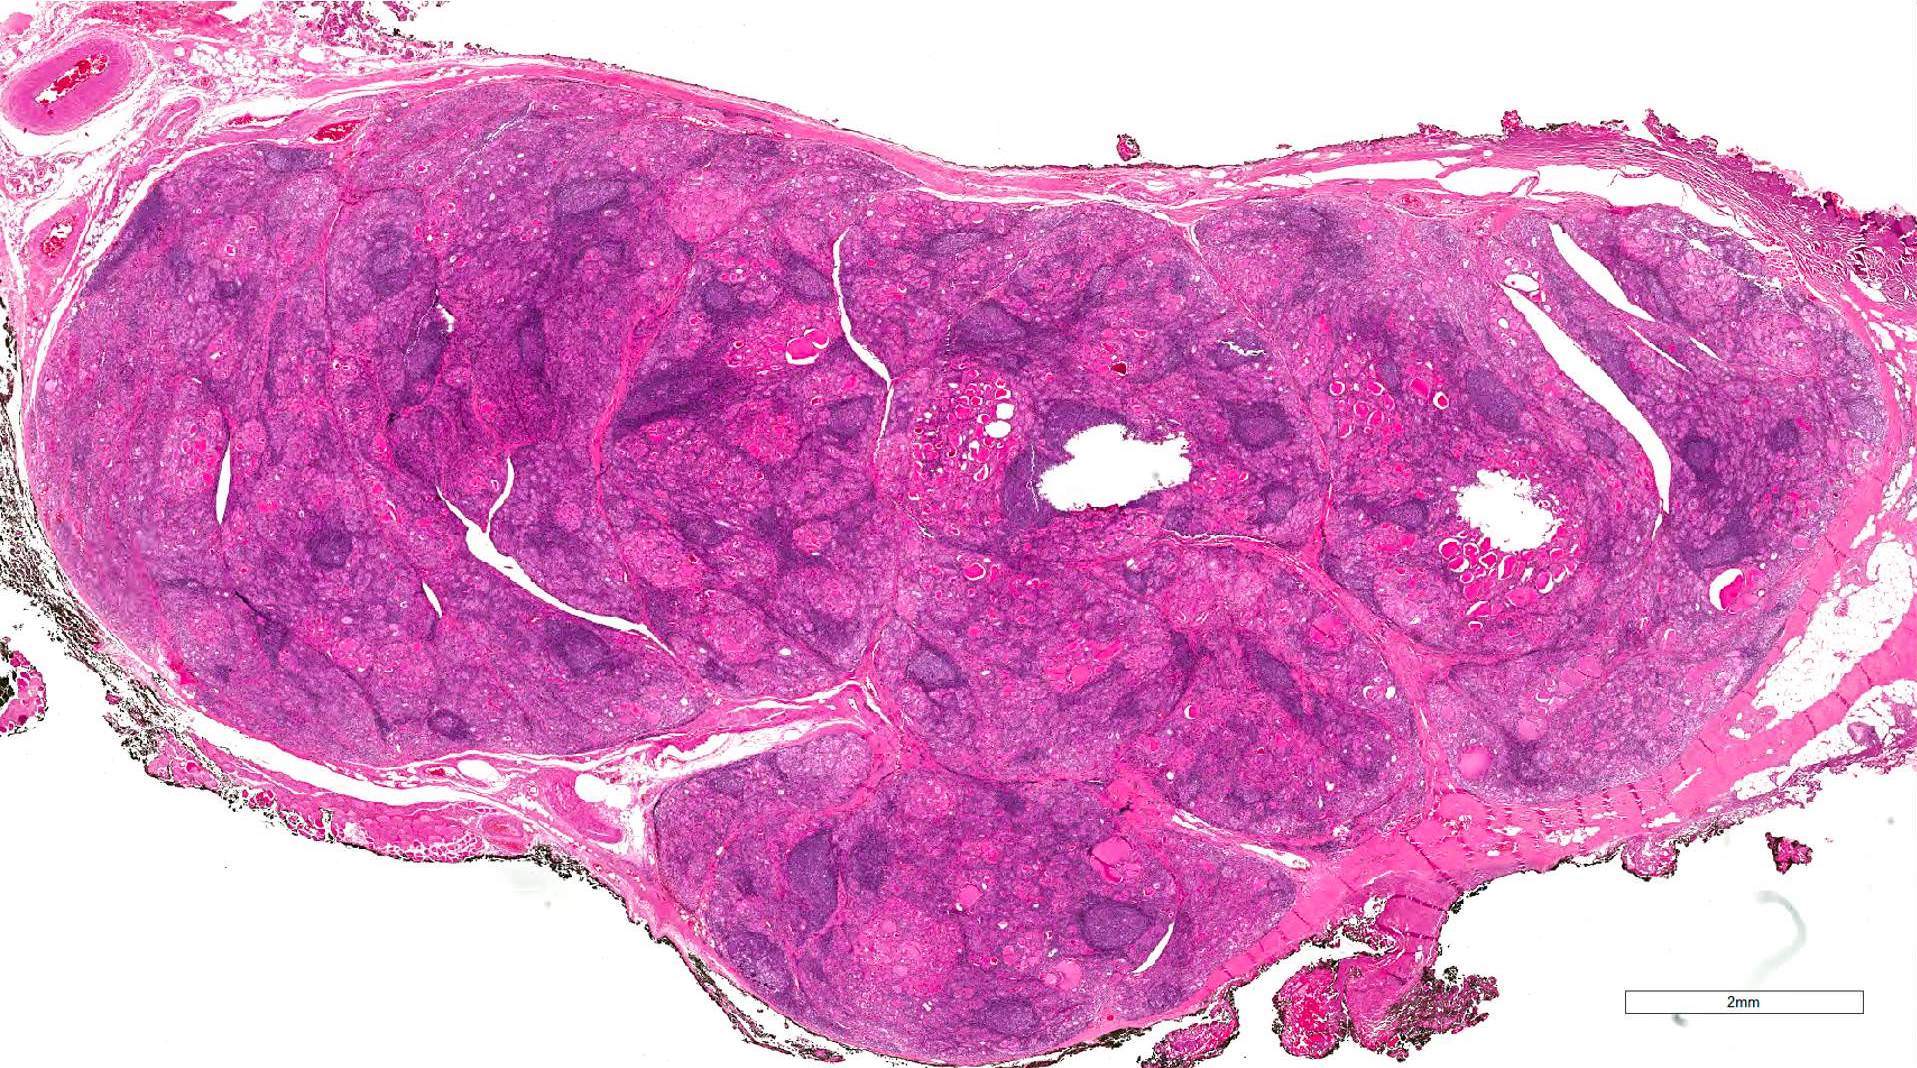

Gross description

- Diffuse symmetric enlargement of thyroid gland; occasionally asymmetric enlargement or nodular

- Cut surface: pale, yellow-tan, firm, nodular; resembles lymph nodes

- May be fibrotic and atrophied

Gross images

Microscopic (histologic) description

- Classic form: diffuse infiltration of thyroid parenchyma with lymphocytes and plasma cells; lymphoid follicle formation with germinal centers (Best Pract Res Clin Endocrinol Metab 2019;33:101367)

- Polymorphic lymphocytic infiltrate, predominantly T cells

- Thyroid follicular destruction

- Atrophic thyroid follicles; many lined by oncocytic cells / oncocytes having abundant granular eosinophilic cytoplasm; rarely squamous metaplasia

- Later fibrosis and nodularity (Virchows Arch 2013;462:557)

Microscopic (histologic) images

Contributed by Andrey Bychkov, M.D., Ph.D. and Shipra Agarwal, M.D.